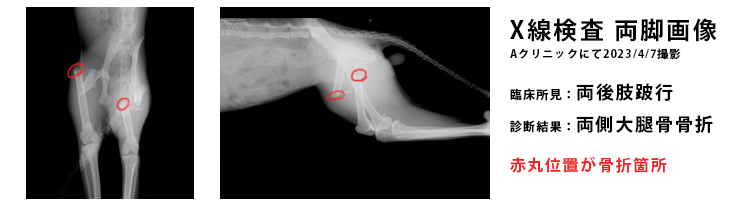

◆2023年4月7日 Aクリニックにて

Aクリニックで、X線検査、耳垢検査をしてもらい「両脚大腿骨骨折」の診断を受けました。

筋肉と骨が間違った位置で癒着してしまうので、「早期手術が必要」といわれました。

整形外科があるH病院を紹介されました。